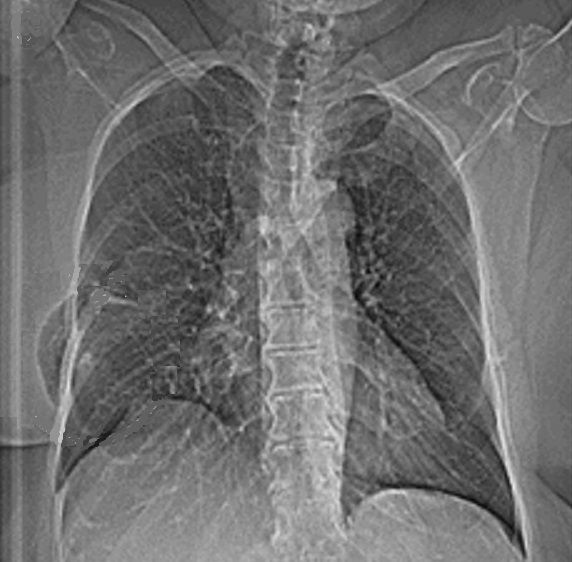

Image radiologique PA d'une

hernie pulmonaire parietale droite après d'une

thoracotomie du tumeur pulmonaire . La

prostruction de la parenchyme pulmonaire est en vue

net de parietal droit du thorax |